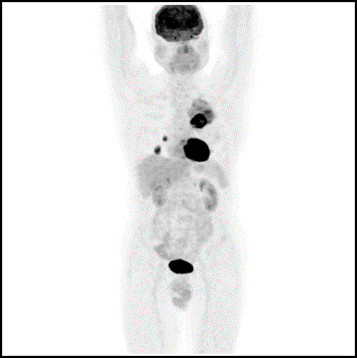

Pacjent 59-letni został skierowany na badanie PET-CT z użyciem 18F-FDG z powodu nacieku w lewym płucu w celu oceny charakteru zmiany. Przedstawiony poniżej obraz z tego badania wskazuje, że jest to: